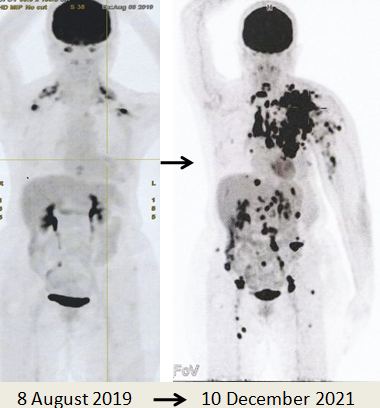

Due to the massive metastasis as shown in the PET scan done on 10 December 2021, Lucy had no choice but to proceed with chemotherapy. Indeed the cancer had spread extensively.

8. PET scan on 14 April 2022 showed good response indeed.

1. Amazing results of chemotherapy. Compare these three pictures –

Left: After surgery Lucy was on alternative therapy, refusing to undergo chemotherapy. The result was extensive metatastasis (middle). Right: Lucy has no choice but to go for chemotherapy. The outcome of 6 cycles of chemotherapy was just fantastic! In my 25 + years dealing with cancer patients, I have never seen such a great outcome of chemotherapy. Salute the oncologist! You rescued her!

In fact, the results were so unbelievable that one is tempted to ask if it is for real and not a fake? My answer is NO, detailed study of the PET scan results below are real! Study the images carefully – those before and after  chemotherapy.

• PET scan showed local recurrence at left chest well, with metastases to regional and distinct lymph nodes, subcutaneous nodules, lung, peritoneum and bones. There is minimal pericardial effusion, metastases cannot be excluded.

As demonstrated by the outcome of this case, Lucy had taken the wrong path. Twenty months after doing what she thought was the right things to do, Lucy’s cancer spread like wild fire. There were metastases to regional and distinct lymph nodes, subcutaneous nodules, lung, peritoneum and bones (see the pictures above).

I may say I could not believe what I saw in the PET scan – it was a terrible disaster indeed. Lucy had committed  a tragic mistake.